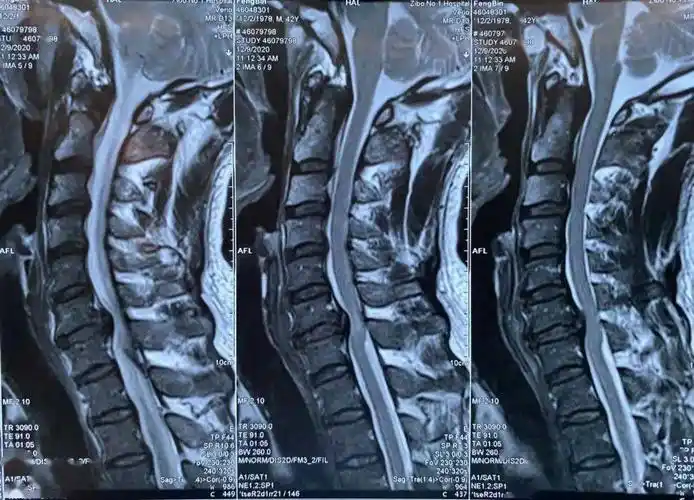

脊髓型颈椎病术前ct片脊髓型颈椎病术前x线正,侧位片患者为42岁男性